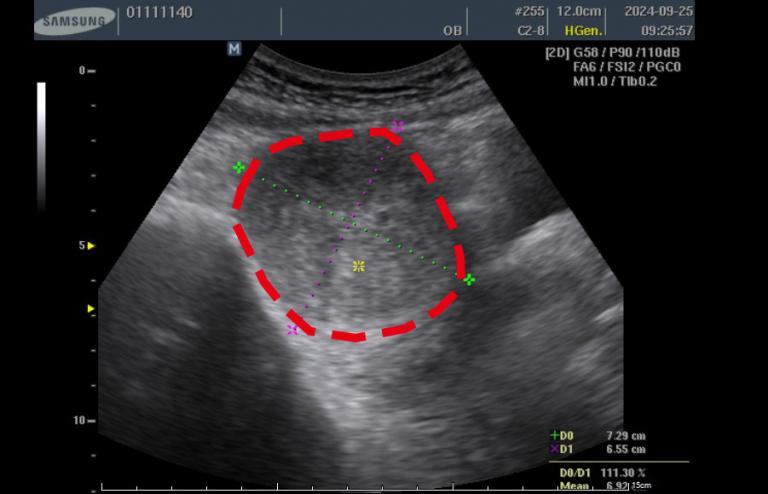

52歲的徐女士長年飽受經痛、頻尿及下腹悶脹等症狀困擾,她在113年9月20日前往林新醫院健檢中心接受檢查時,經婦產科超音波檢查發現,她的子宮前壁長有一顆約 7.3×6.5×6.2 公分、體積達294立方公分的子宮肌瘤,大小約等同一顆中型芒果,且已壓迫膀胱,導致她日常需頻繁如廁、夜間多次起床影響睡眠,外出時也須時時留意洗手間位置,生活品質明顯受到影響。

▲徐女士的子宮前壁長有一顆約 7.3×6.5×6.2 公分、體積達294立方公分的子宮肌瘤,大小約等同一顆中型芒果,且已壓迫膀胱,導致她日常需頻繁如廁,生活品質明顯受到影響。(圖╱林新醫院提供)